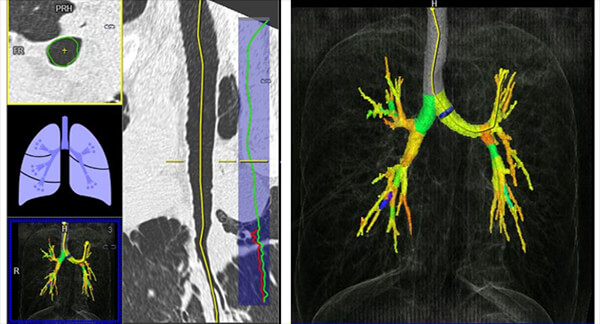

Bronchial Tree

This image shows us the visualization of the bronchial lumen and its caliber.

Emphysema Measurement

The automated application called “lung density” provides the physician with quantitative data on the volume of pulmonary emphysema, as well as gives us a visual representation of its diffusion.

Damaged Alveoli

This image shows us an example of images where the damaged alveoli are highlighted in blue.

Percentage of Lung Parenchyma

Here, we can see the percentage of lung parenchyma in function of Hounsfield densities.

HU Measurements